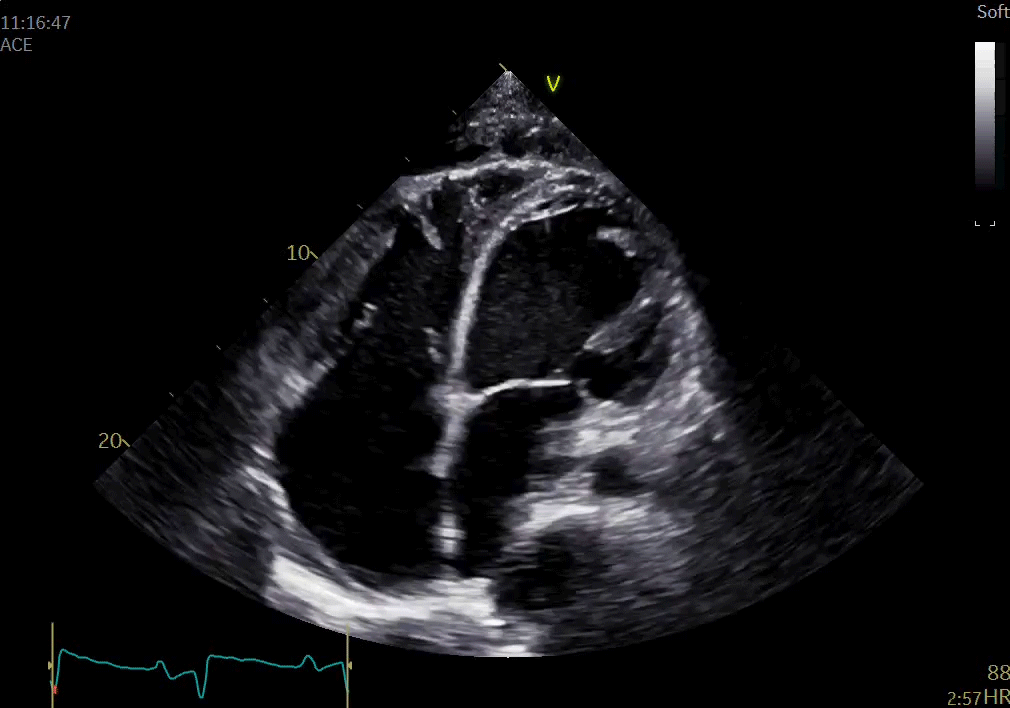

Vivid E95